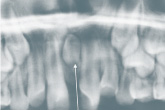

Das ist ein überzähliger, meist atypisch geformter oder verkümmerter Zahn zwischen den mittleren Schneidezähnen 11 und 21, in seltenen Fällen auch zwischen

den Unterkieferschneidezähnen 31 und 41. Weil ein Mesiodens nur in seltenen Fällen spontan durchbricht, ist er meist nur röntgenologisch nachweisbar. Ansonsten kann er einfach

gezogen werden. In der Regel muss er operativ entfernt werden.